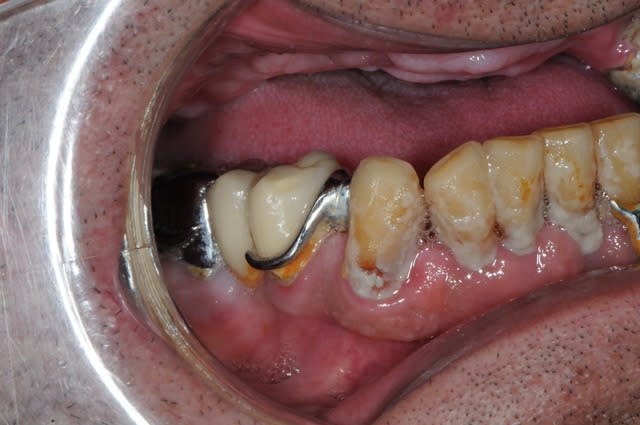

Oui bien sûr placé sous 48 h

Les piliers seront retirés sur les molaires par la suite

Pp

Pour me faire un idée...

c'est combien le devis de cette arcade d'implants,

au total. Merci